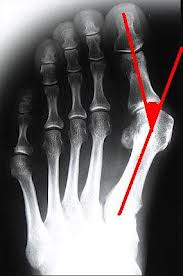

但是比起一些很嚴重的案例來說, 我的外翻角度算是輕微(15度以內), 我看過很凸的, 也看過有人大拇趾和第二趾重疊的.

陳醫師覺得我的角度很小, 建議我暫時不要開刀, 改用泡熱水, 用手扳開拇趾, 按摩突出的骨頭等方式來減輕抽痛的頻率, 等到真的痛到不行, 痛的時間很長, 影響日常作息的時候, 他就會幫我開刀. 他說現在的開刀方式和以前不同, 不但矯正骨頭的位置, 連韌帶都要調整位置, 這樣才不會有復發的問題, 而且傷口很小, 復原時間短, 開刀隔天就可以下床, 二週後回診沒問題後我就可以回美國 (如果未來要開刀的話).